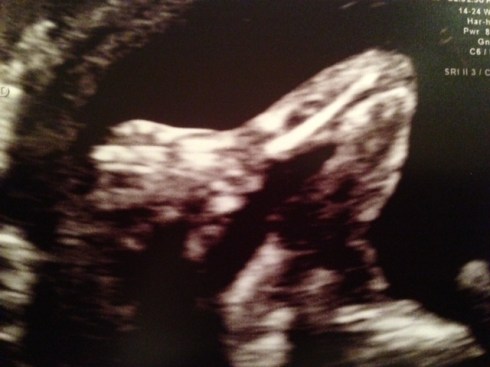

Supposedly, we’ll have another baby GIRL in four months and change!

Our anatomy scan last week went well–heart, kidneys, spine, brain, diaphragm, limbs, etc. all look healthy and appropriately sized. But little Miss Modest kept her legs crossed. The fellow resolved, “Well, I don’t see a penis.” So we could still be surprised on b-day.